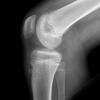

what is this finding called? association?

Segund fx

bony aculsion of anterolateral ligament

pathognominic for acl tear

associated with acl tear 75-100 percent of the time.